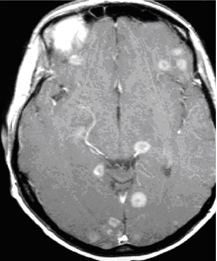

Hình 4. Hình ảnh u di căn não đa ổ dạng đặc, dạng nang và ngấm thuốc dạng vòng trên phim T1 có tiêm thuốc của bệnh nhân ung thư vú

Hình 5. Hình ảnh u di căn não với nhiều tổn thương nhỏ, ngấm thuốc dạng vòng được phát hiện trên T1 có tiêm thuốc của bệnh nhân ung thư phổi